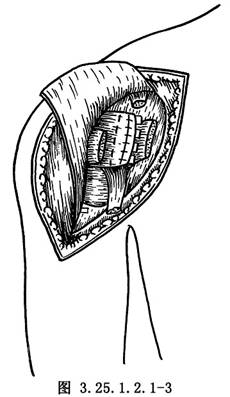

分開三角肌,由喙突上切斷喙肱肌及肱二頭肌短頭的起點,向下翻轉,切開胸大肌上緣一部分,切斷小結節處肩胛下肌止點,顯露關節囊(圖3.25.1.2.1-3)。